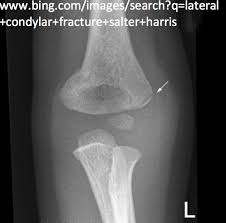

10+ Elbow Anatomy Xray. Elbow injuries have characteristic appearances. This is an online quiz called elbow xray anatomy.

Soft tissue abnormality is often the only evidence of bone injury.